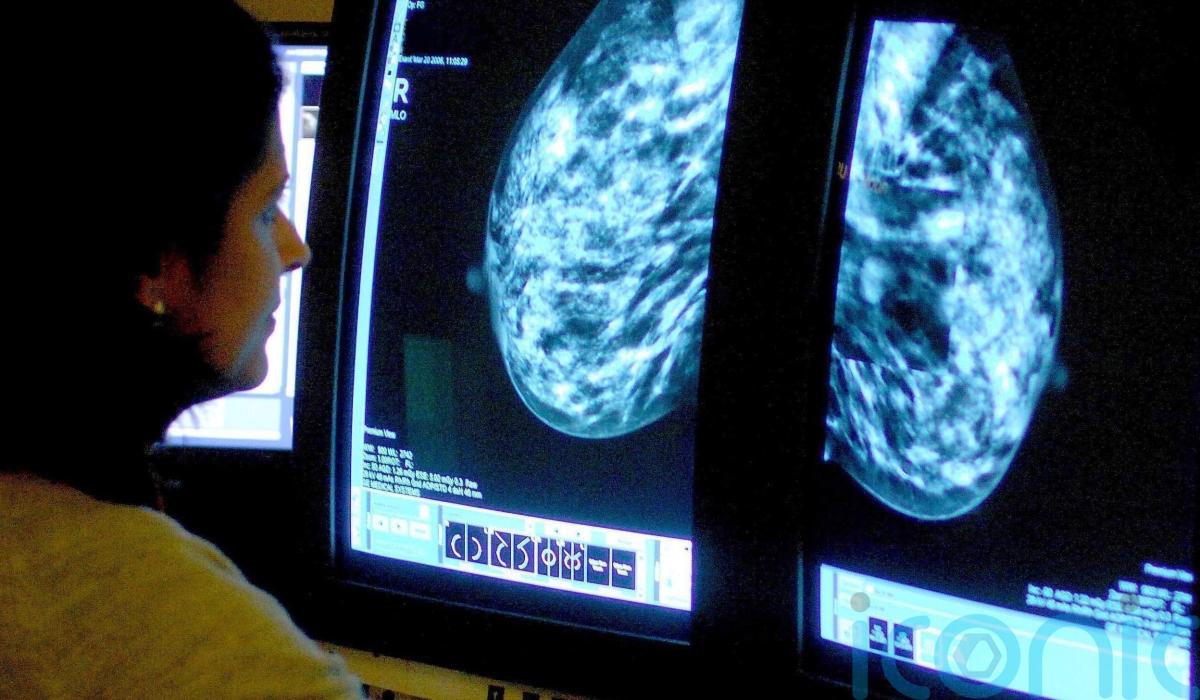

One in 20 women referred urgently for breast cancer were seen within two weeks last winter, figures released by the Department of Health show.

From October to December 2025, 3,902 patients were seen by a breast cancer specialist after an urgent referral across all five HSC Trusts, 44.6% more than in the previous quarter.

Some 5.5% of those patients were seen within 14 days of an urgent referral for breast cancer, compared with 6.8% in the previous period.